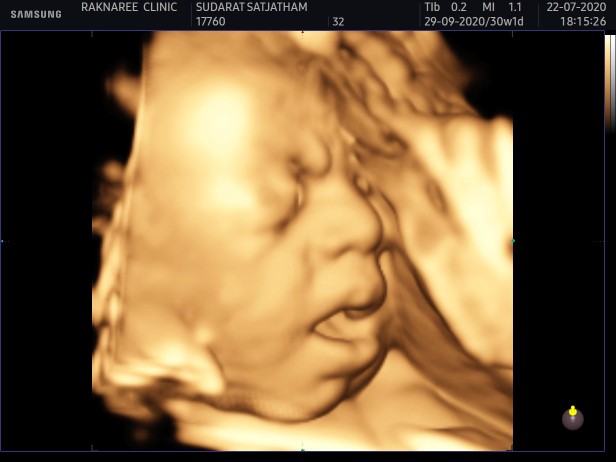

ภาพซาวน์ตอน30wค่ะ